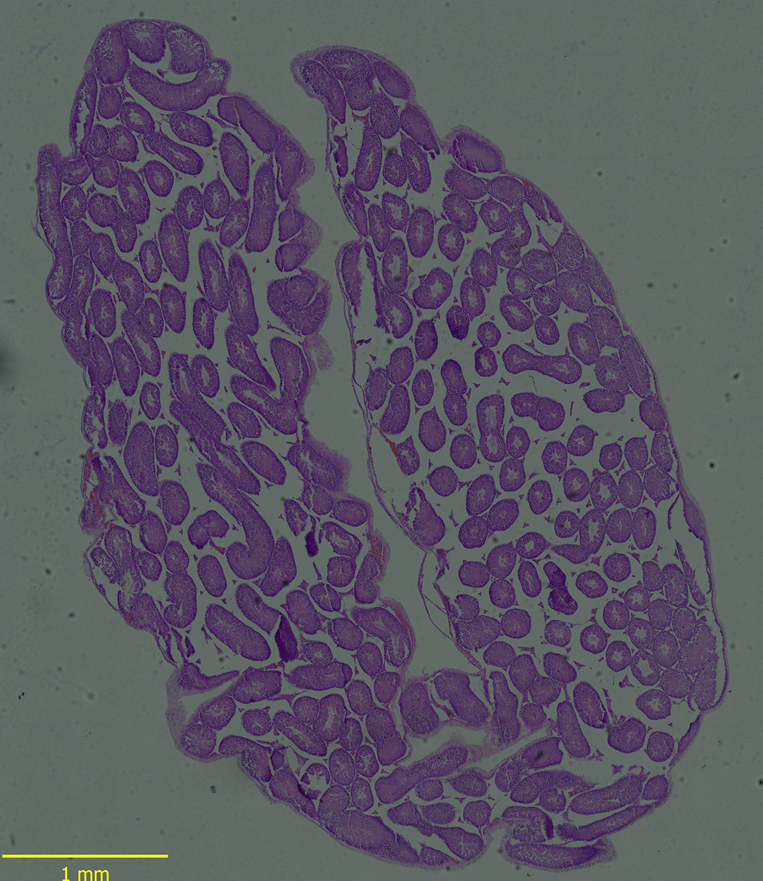

比较CELENA®X Cell Analyzer软件和A公司的软件的图像拼接质量。利用同一样本中获得图像,对图像拼接算法进行比较。A公司软件拼接的图像存在畸变和错位误差,难以准确理解每个样品的整体形态。(图2)。然而CELENA®XCell Analyzer软件成功生成无明显误差的无缝图像(图2B)。

图2.(A)H&E染色切片的图像拼接结果:公司A的图像结果显示不齐和失真问题,CELENA®X Cell Analyzer软件拼接无缝图像(301 X 423像素)。(B)使用小鼠脑样本的图像拼接结果:A公司的图像结果与使用CELENA®X Cell Analyzer软件的结果图像和无缝图像结果相比,显示出不对齐和失真问题(471 x 662像素)。

小鼠睾丸组织HE染色切片(20X)